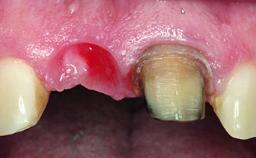

A 36-year-old male patient with a compromised maxillary central incisor was referred by his general dentist for consultation. The patient’s chief complaints were the gradual debonding of a temporary crown on the right central incisor and unsatisfactory esthetics due to an increasing diastema between the right central and lateral incisors. The patient reported a traumatic event some years previously, when a crown had been placed after root-canal treatment. The referring dentist wanted to provide a new crown restoration, but was concerned about the condition of the residual root. Anamnesis was negative for any other dental or periodontal pathology in the remaining dentition. The patient reported taking no medications: He was a smoker (10 to 15 cigs/day) and had realistic esthetic expectations.